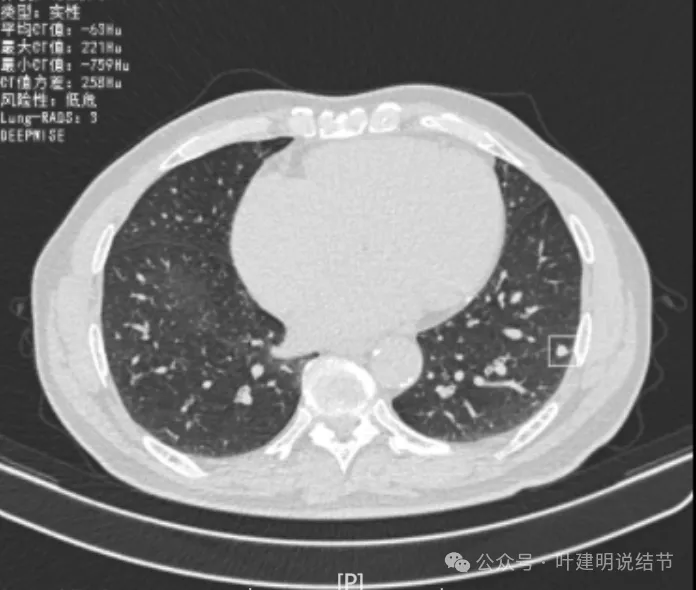

再看2022年8月复查时AI报告找出来的影像:

多是微小实性结节,主要的仍是右上与左下的这两处,较3月时无明显变化。而右下原来似有微小结节处这次并不明显。